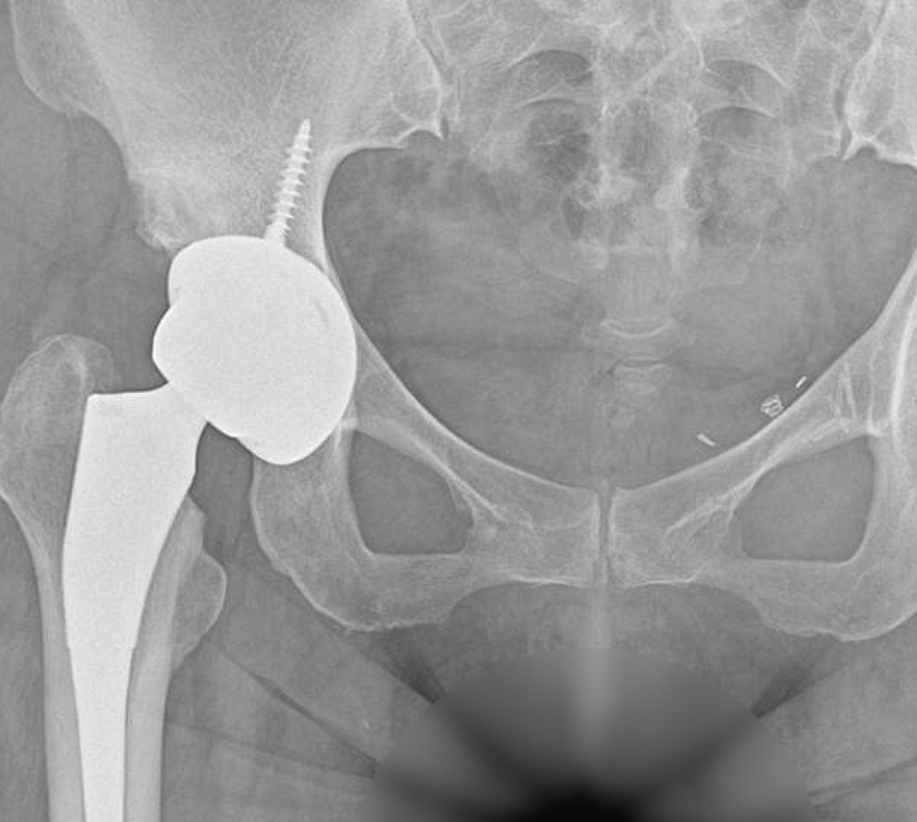

고관절 통증 증상은 조기에 발견하고 치료받는 것이 무엇보다 중요합니다. 고관절 손상이 심하지 않고 통증이 가볍다면 약물치료와 운동치료 등 보존적 치료를 통해 회복할 수 있습니다. 하지만 고관절 손상이 심하고 일상생활에 지장을 줄 만큼의 심한 고관절 통증 증상이 있는 경우라면 괴사된 관절을 제거하고 인공관절을 삽입하는 고관절의 인공관절 치환술을 해야 합니다.